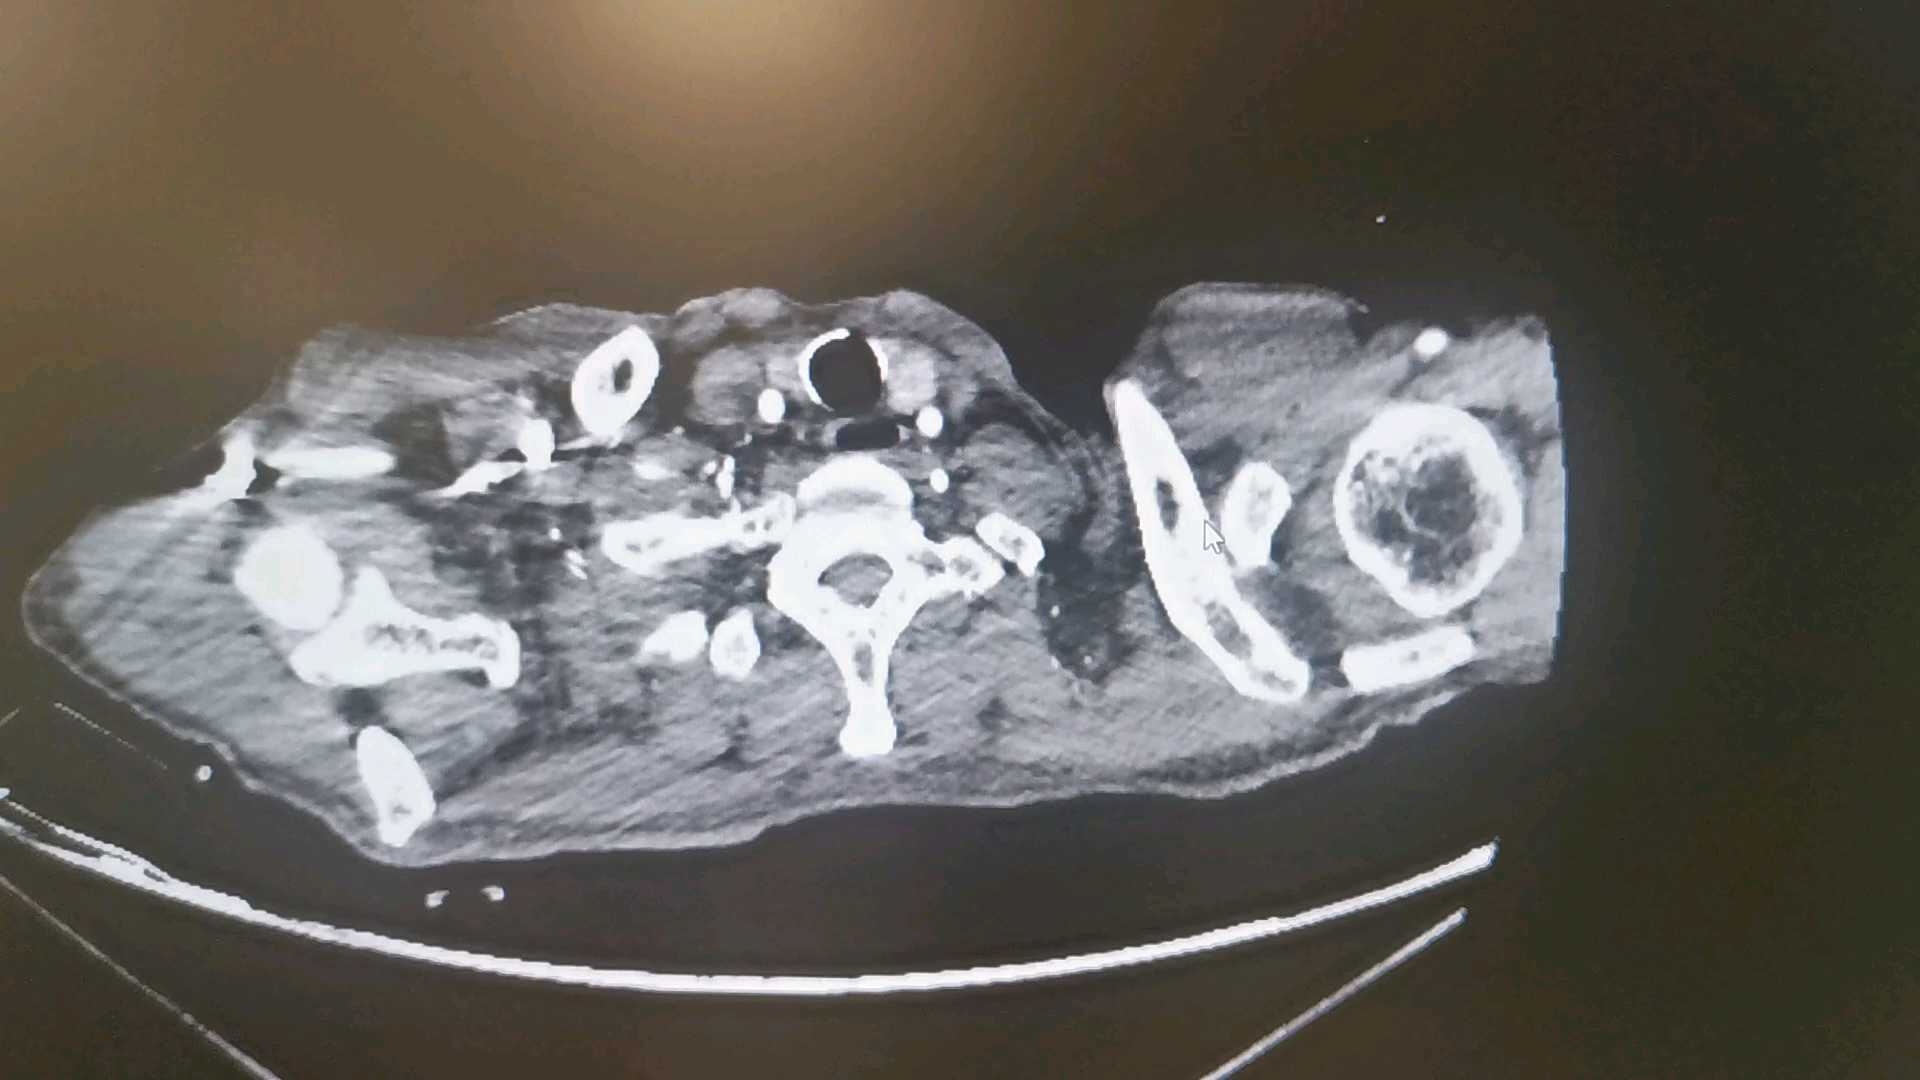

排除手木禁忌后行食管支架置入术,术后给予营养支持、补液、抗感染等治疗。11-17给予亚胺培南西司他汀钠1g q6h抗感染,同时给予静脉营养,持续心包引流,引流液为黄色脓性液体。11-17患者夜间出现频发房颤、室早,给予艾司洛尔泵入。11-18行心脏彩超示下腔静脉增宽,二尖瓣返流(轻度),三尖瓣返流(轻度),提示左室充盈异常,心包积液(少量)。心内科会诊建议继续抗感染治疗,复查血钾,艾司洛尔静脉泵入。心脏外科会诊示保持心包引流通畅,必要时行冲洗治疗,留取引流液行病原学检查;目前暂无拔管指征,待引流液性质清亮,连续2天小于50m可考虑拔管。11-20行增强CT检查: